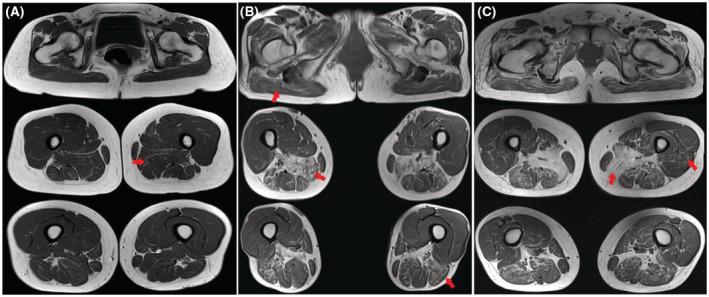

In our cohort, the genetically confirmed OPMD group had a mean age at onset of 50.6 ± 4.2 years (range 45-60 years). Ptosis (42.9%) was the most common initial symptom; patients with ptosis as the first symptom subsequently developed dysphagia within a median time of 5.5 years (range 1-19 years). Evidence of external ophthalmoplegia was found in 38.1% of patients. A total of 33.3% of the patients developed muscle weakness at a median age at onset of 66 years (range 50-70 years), with neck flexor involvement in all patients. Five genotypes were observed in our cohort, including classical (GCG)9-11 repeats in 7 families and non-GCG elongations with additional GCA expansions in 2 families. OPMD muscle biopsies revealed rimmed vacuoles and intranuclear filamentous inclusions. The PABPN1 protein showed substantial accumulation in the nuclei of muscle fiber aggregates and closely colocalized with p62, LC3B and FK2.

在我们的队列中,基因确诊的 OPMD 组发病年龄的平均值为 50.6±4.2 岁(范围 45-60 岁)。上睑下垂(42.9%)是最常见的首发症状;首发症状为上睑下垂的患者随后在中位数 5.5 年内(范围 1-19 年)发展为吞咽困难。38.1%的患者存在外眼肌麻痹的证据。33.3%的患者在中位数发病年龄 66 岁(范围 50-70 岁)时出现肌肉无力,所有患者均有颈屈肌无力。我们的队列中观察到 5 种基因型,包括 7 个家系中的经典(GCG)9-11 重复和 2 个家系中的非 GCG 延长伴额外的 GCA 扩展。OPMD 肌肉活检显示边缘空泡和核内丝状包涵体。PABPN1 蛋白在肌纤维聚集物的核内大量堆积,并与 p62、LC3B 和 FK2 紧密共定位。